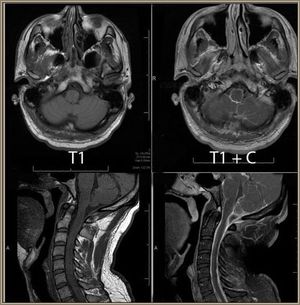

Differential Diagnosis of Meningitis and Encephalitis

ByMurtaza Khan, MD,Amanda L Piquet, MD

The authors distinguish between the clinical entities of meningitis, encephalitis, and encephalopathy.